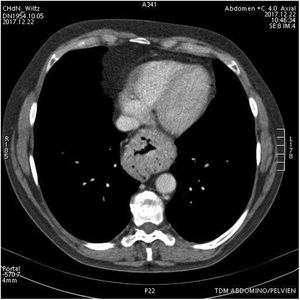

Caso clínicoSe trata de una paciente de 65 años diagnosticada de hernia de hiato sintomática de 2años de evolución. A pesar del tratamiento conservador, con recomendaciones posturales y dietéticas, y de inhibidores de la bomba de protones, la paciente presenta empeoramiento de la clínica de reflujo gastroesofágico. El control radiológico muestra incremento del tamaño de la hernia de hiato de 4cm (de 2cm a 6cm) (figs. 1-3). Preoperatoriamente se realiza una endoscopia que informa de gastritis y esofagitis en ausencia de esófago de Barret y lesiones neoplásicas. Ante el diagnóstico de hernia de hiato sintomática resistente al tratamiento y sospecha diagnóstica de esófago corto, se indica tratamiento quirúrgico.